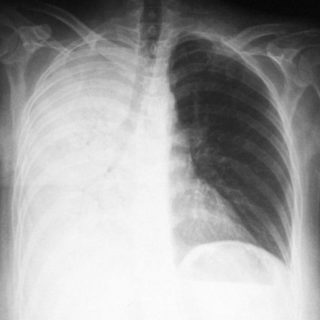

Если есть проблемы с дыханием, возможно это пневмония, которая отдает в нижнюю часть спины

- Пневмония. Если в воспалительный процесс включается поражение плевры, боль отдает даже в поясницу, конечности, другие части тела. Боль становится острой, усиливающейся при вдохе, простреливающей. Может сопровождаться кашлем, температурой, трудностями с дыханием, отдает под лопатки и в область грудины. У пациента наблюдается тяжелое, хриплое дыхание.